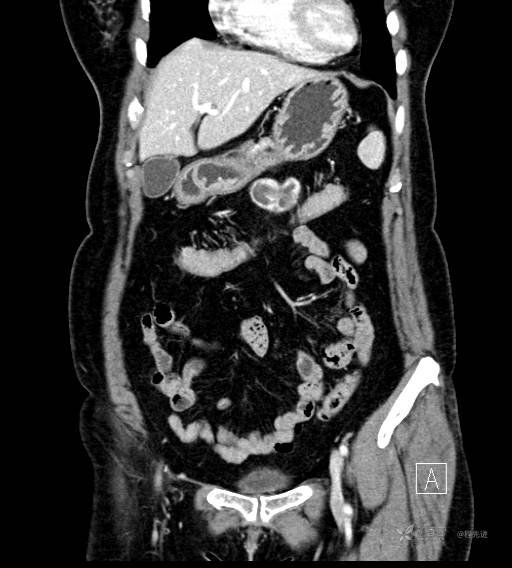

CT增强动脉期